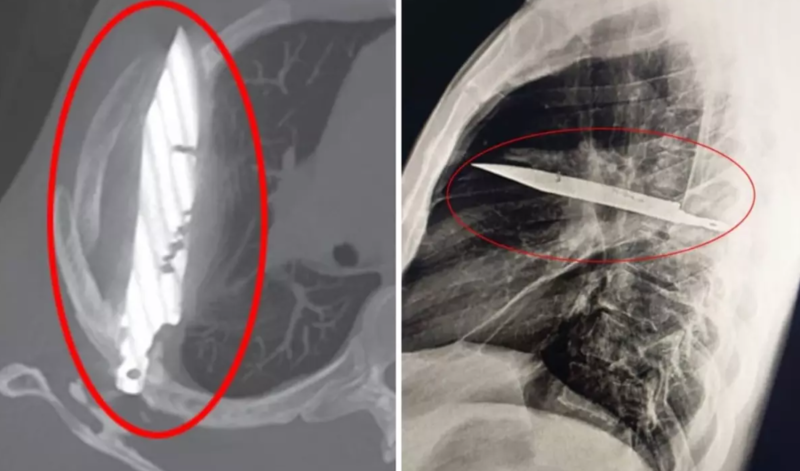

Sonxeber.az türk mediasına istinadən xəbər verir ki, həkimlər ilkin müayinədə ağrı, nəfəs darlığı, öskürək və ya hərarət kimi əlamətlər aşkar etməsə də, rentgen nəticəsi hər kəsi təəccübləndirib – kişinin döşündə tam 8 ildir qalmış bıçaq tapılıb.

Pasiyent illər əvvəl yaşadığı şiddətli dava zamanı üzündən, kürəyindən, döşündən və qarın nahiyəsindən yaralandığını, həmin vaxt müalicə olunduğunu, o gündən bəri isə ciddi sağlamlıq problemi yaşamadığını bildirib. Son günlər yaranan irinlənmə səbəbindən həkimə müraciət edən kişinin döşündə illərlə "unudulmuş" bıçaq aşkarlanıb.

Məlum olub ki, bıçaq sağ kürək sümüyündən girərək həyati orqanlara toxunmadan döşdə qalıb. Əməliyyat zamanı bıçaq çıxarılıb, ölü toxumalar təmizlənib. Pasiyent reanimasiyada bir gün, normal palatada isə 10 gün qalıb. Həkimlər onun tam sağaldığını açıqlayıb.